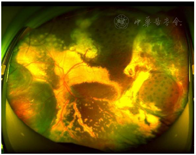

裂隙灯检查:双眼眼前节及右眼眼底检查未见明显异常,左眼眼部检查见大量黄白色渗出及点片状出血,颞侧可见视网膜下增殖膜,鼻下方见局部视网膜球形隆起(图1)。